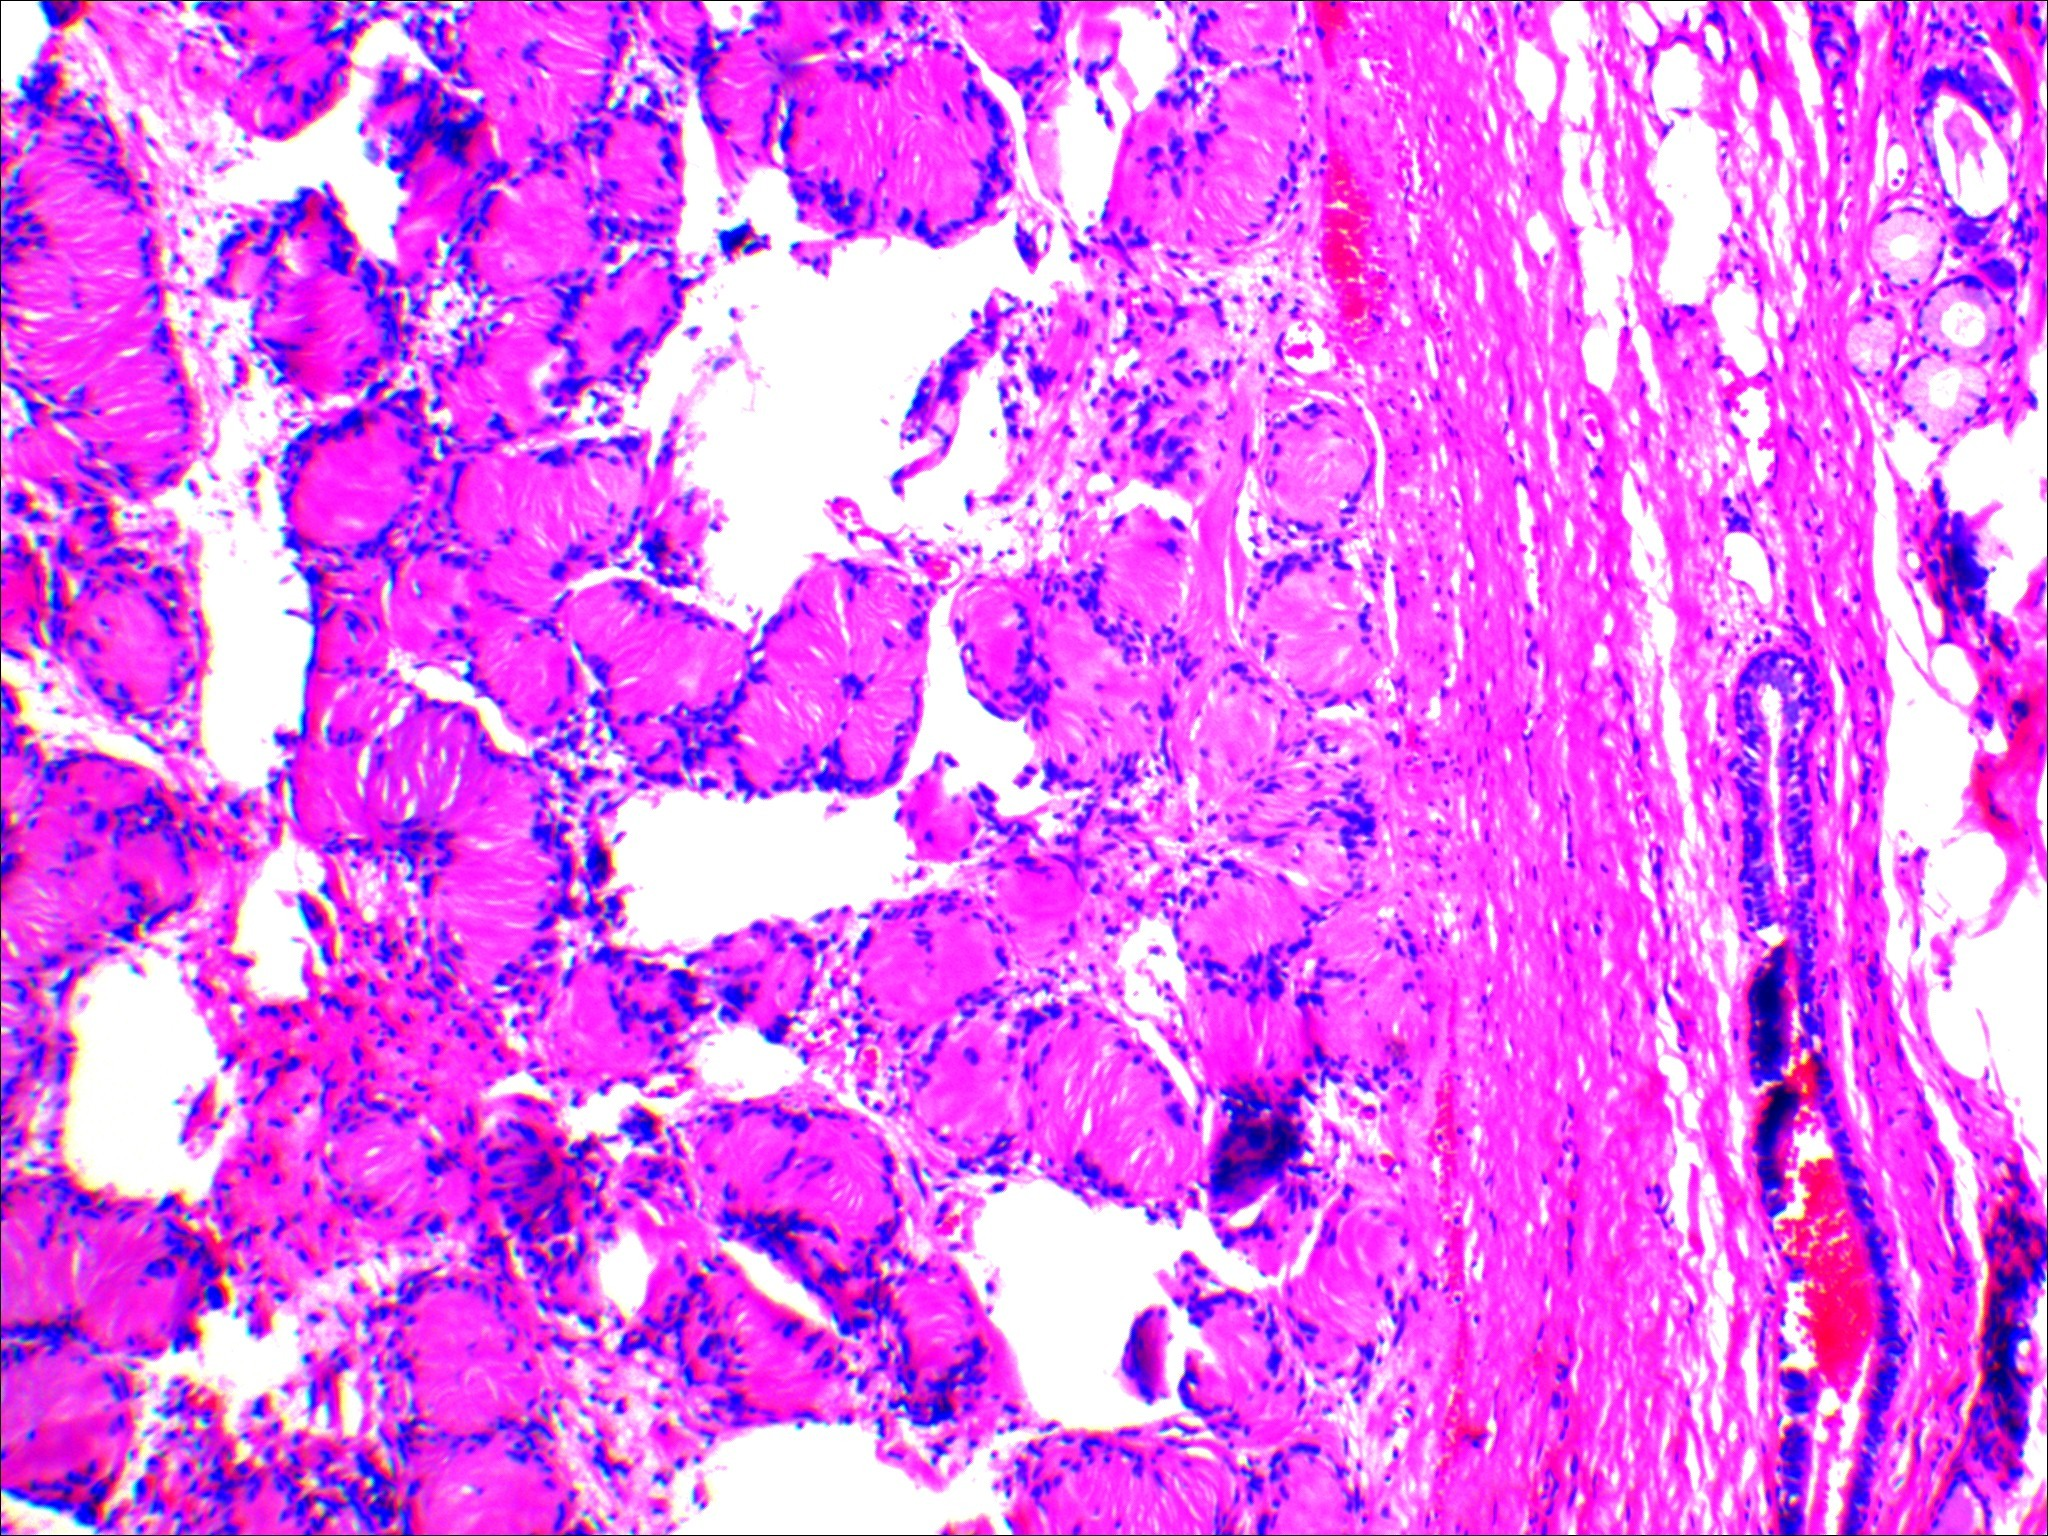

神经鞘瘤显微镜形态(图片来源于作者本人)

病理诊断:(左肺上叶结节)神经鞘瘤

神经鞘瘤又称为施万瘤或许旺瘤,是一种相对少见的神经源性肿瘤,约占原发神经源性肿瘤的第2位。该肿瘤发生于肺内者非常罕见。